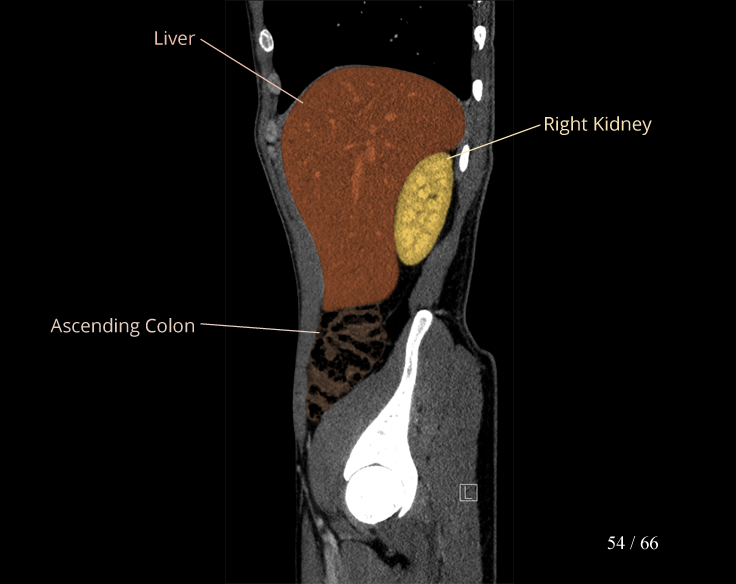

Body

Covers abdominal CT anatomy.